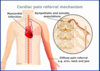

What is a myocardial infarction?

Part of the heart muscle DIES!

What is angina pectoris?

Chest pain/pressure usually due to not enough blood flow to heart muscle